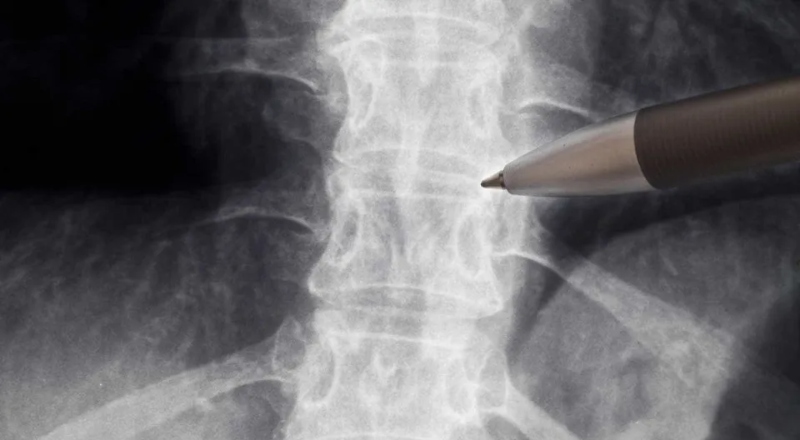

Brasil – A Agência Nacional de Vigilância Sanitária (Anvisa) autorizou o início do estudo clínico para avaliar a segurança do uso do medicamento polilaminina no tratamento do trauma raquimedular agudo, que é uma lesão da medula espinhal ou coluna vertebral.

Segundo Padilha, a pesquisa já apresentou resultados promissores na recuperação de movimentos. Nesta primeira fase, o estudo da polilaminina será realizado em cinco pacientes voluntários com lesões agudas da medula espinhal torácica entre as vértebras T2 e T10.

Essas pessoas incluídas no estudo devem ter indicação cirúrgica ocorrida a menos de 72 horas da lesão. Os locais de realização ainda serão definidos pela empresa responsável. Ao longo da estruturação do projeto, o Ministério da Saúde investiu os recursos para a pesquisa básica.